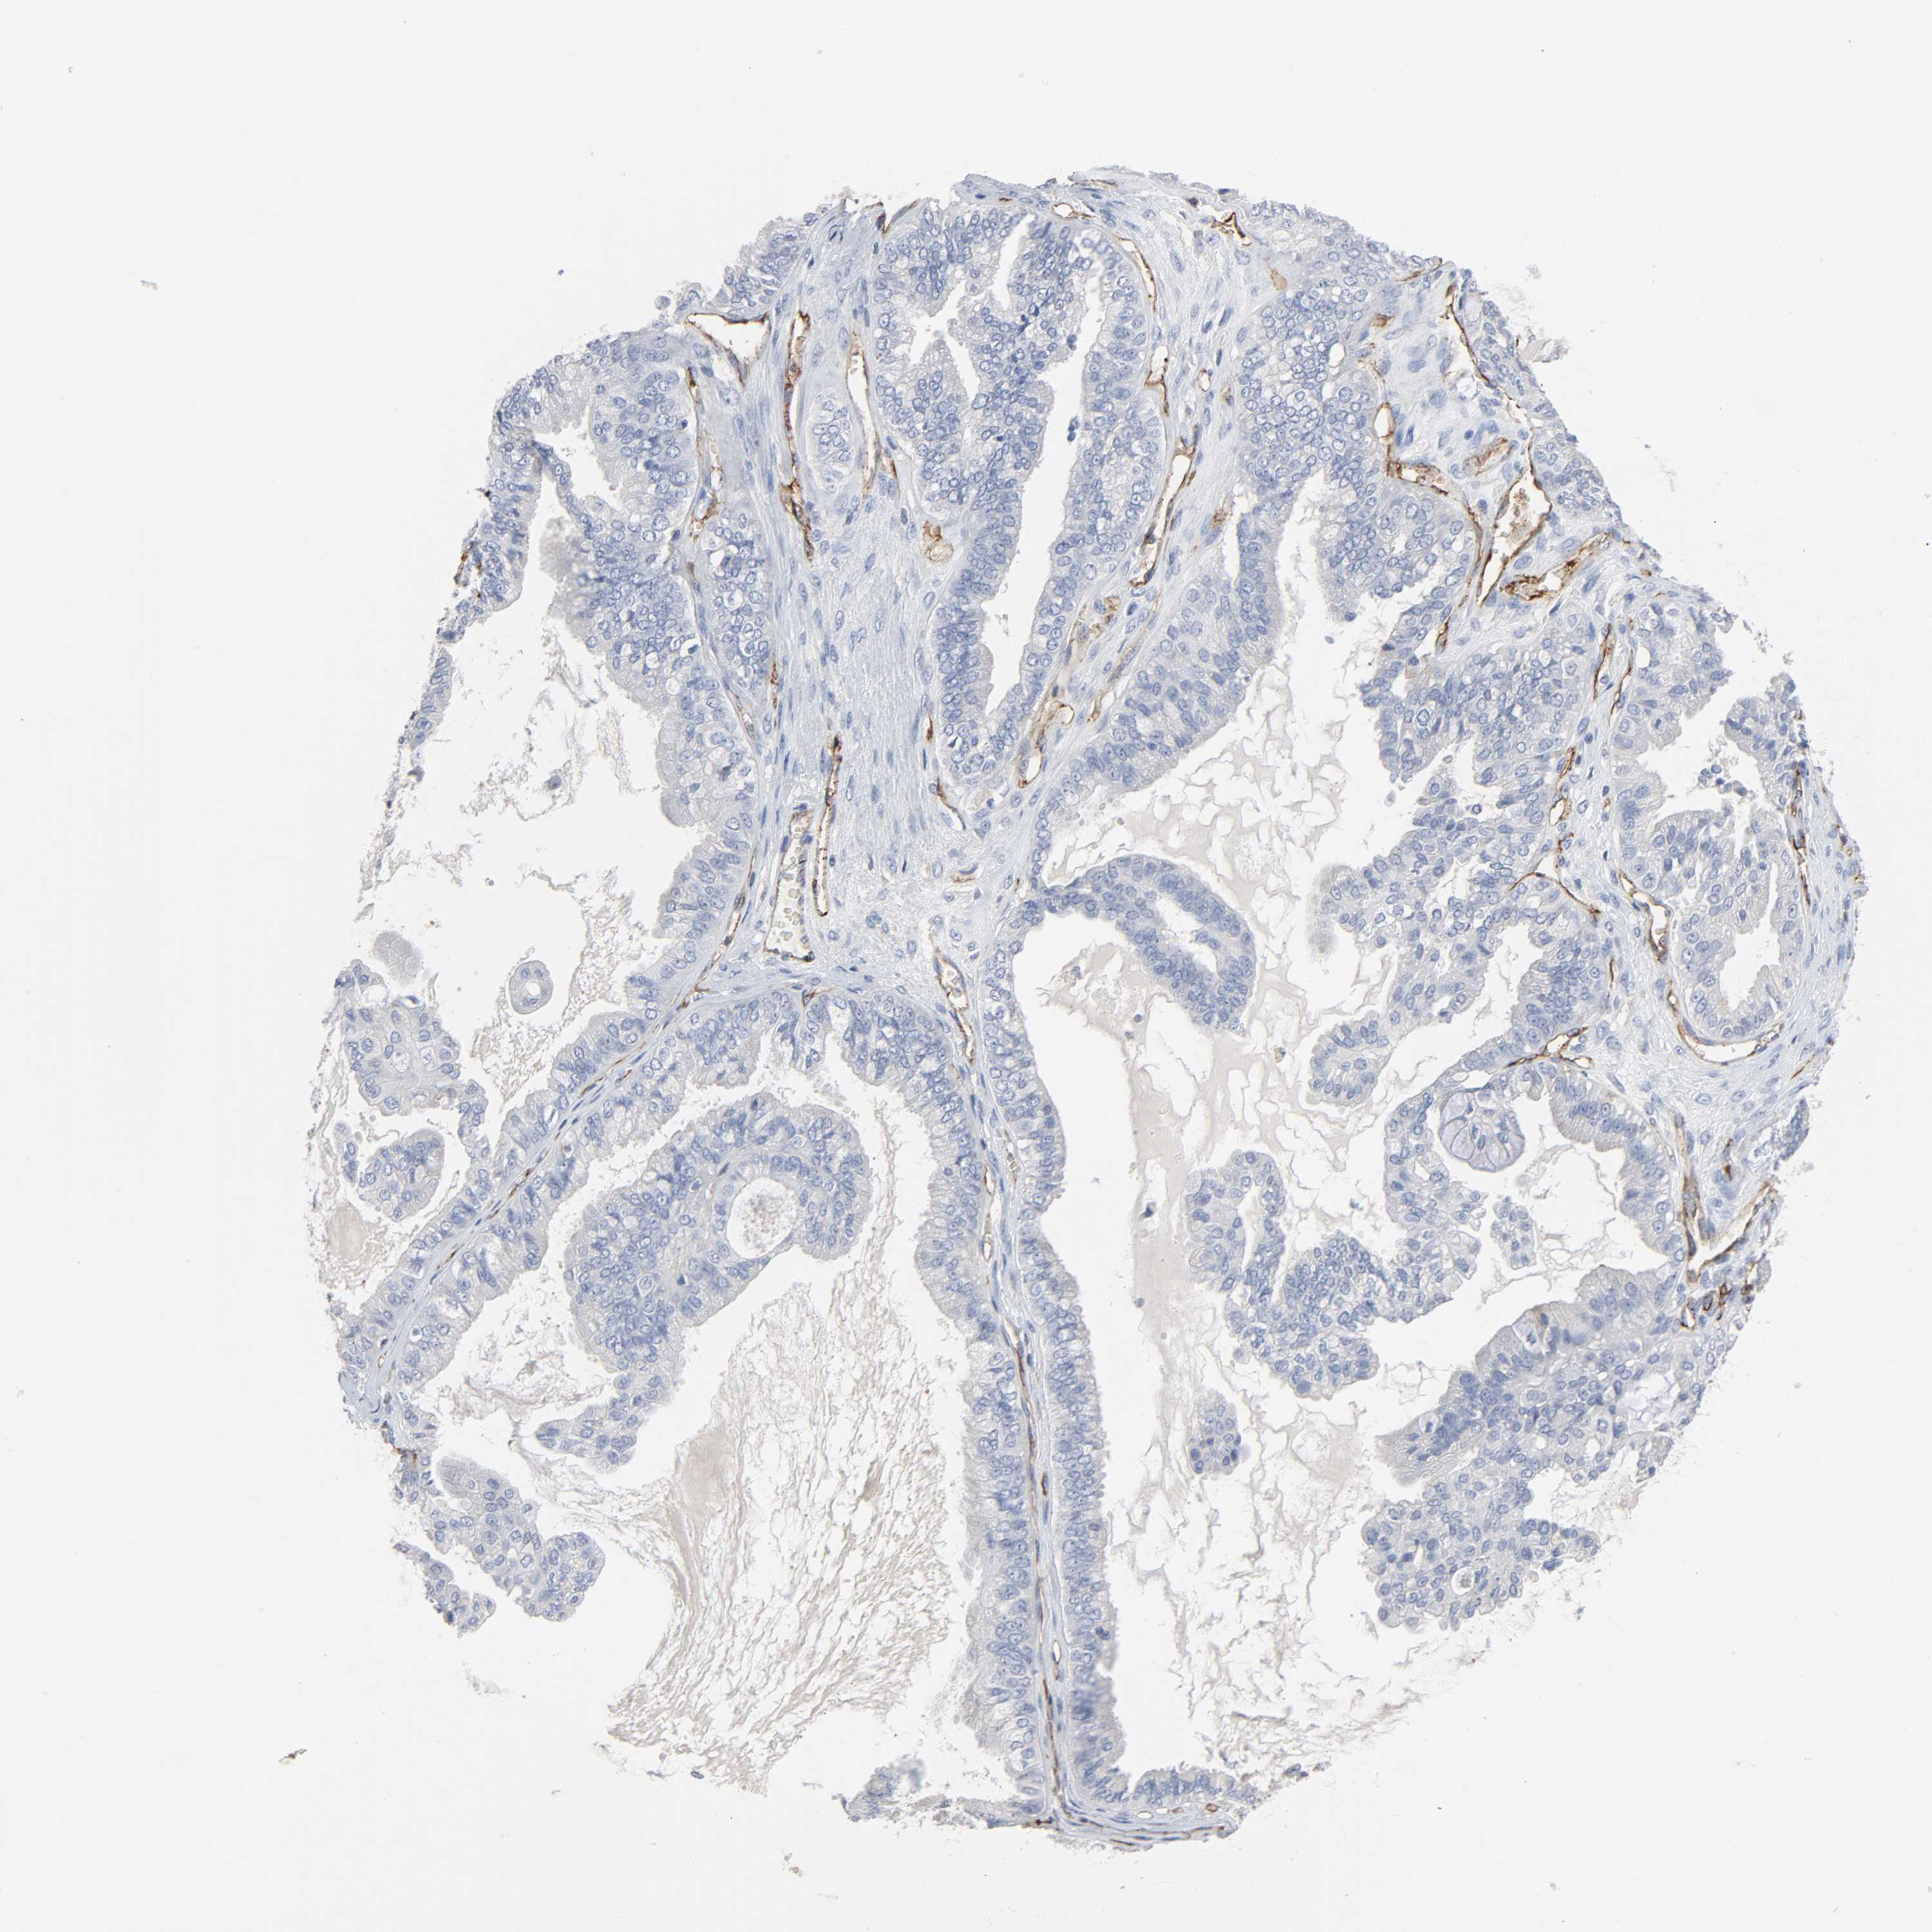

OVARIAN CANCER - Protein expressioni

A mouse-over function shows sample information and annotation data. Click on an image to view it in a full screen mode. Samples can be filtered based on level of antibody staining by selecting one or several of the following categories: high, medium, low and not detected. The assay and annotation is described here.

Note that samples used for immunohistochemistry by the Human Protein Atlas do not correspond to samples in the TCGA dataset.

Antibody stainingi

Antibody staining in the annotated cell types in the current human tissue is reported as not detected, low, medium, or high, based on conventional immunohistochemistry profiling in selected tissues. This score is based on the combination of the staining intensity and fraction of stained cells.

Each image is clickable and will lead to virtual microscopy that enables deeper exploration of all samples and also displays staining intensity scores, fraction scores and subcellular localization as well as patient and tissue information for each sample.

Antibody HPA004690

Staining

High

Medium

Low

Not detected

Intensity

Strong

Moderate

Weak

Negative

Quantity

>75%

75%-25%

<25%

None

Location

Nuclear

Cytoplasmic/membranous

Cytoplasmic/membranous,nuclear

Cystadenocarcinoma, serous, NOS

Carcinoma, endometroid

Carcinoma, NOS

Cystadenocarcinoma, mucinous, NOS